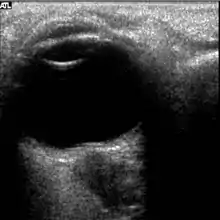

The fourth case of visual changes on orbit was significant for a history of transsphenoidal hypophysectomy for macroadenoma where postoperative imaging showed no residual or recurrent disease. Approximately 2 months into the ISS mission, the astronaut noticed a progressive decrease in near-visual acuity in his right eye and a scotoma in his right temporal field of vision.[5]

Figure 5: On-orbit ultrasound of posterior orbit of the fourth case of visual changes from long-duration spaceflight. In-flight ultrasound image of the right eye showing posterior globe flattening and a raised optic disc consistent with optic-disc edema and raised ICP.